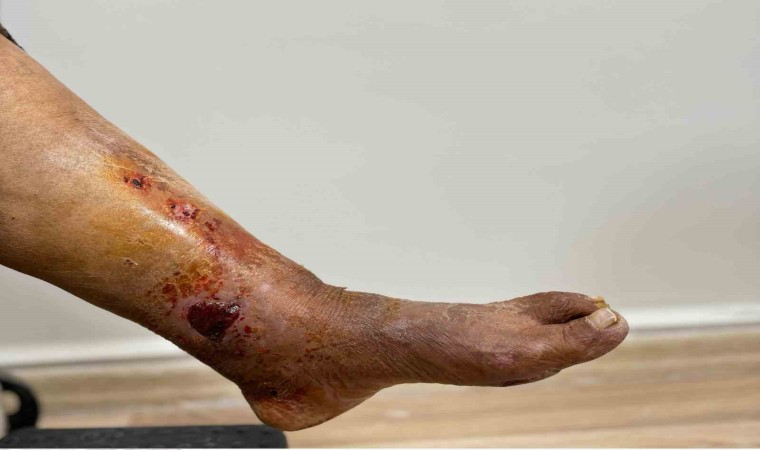

Adıyaman’da 86 yaşındaki H.T., ayak bileğindeki kırıklar nedeniyle Kahta Devlet Hastanesi’ne başvurdu. Ameliyat sırasında narkoz kullanılması durumunda hayati riskler ortaya çıkabileceğinden, hastaya narkozsuz bir ameliyat önerildi. H.T., Ortopedi Uzmanı Op. Dr. İbrahim Halil Cebe tarafından Kahta’da ilk kez Walant Tekniği kullanılarak narkozsuz bir şekilde başarılı bir ameliyat geçirdi.